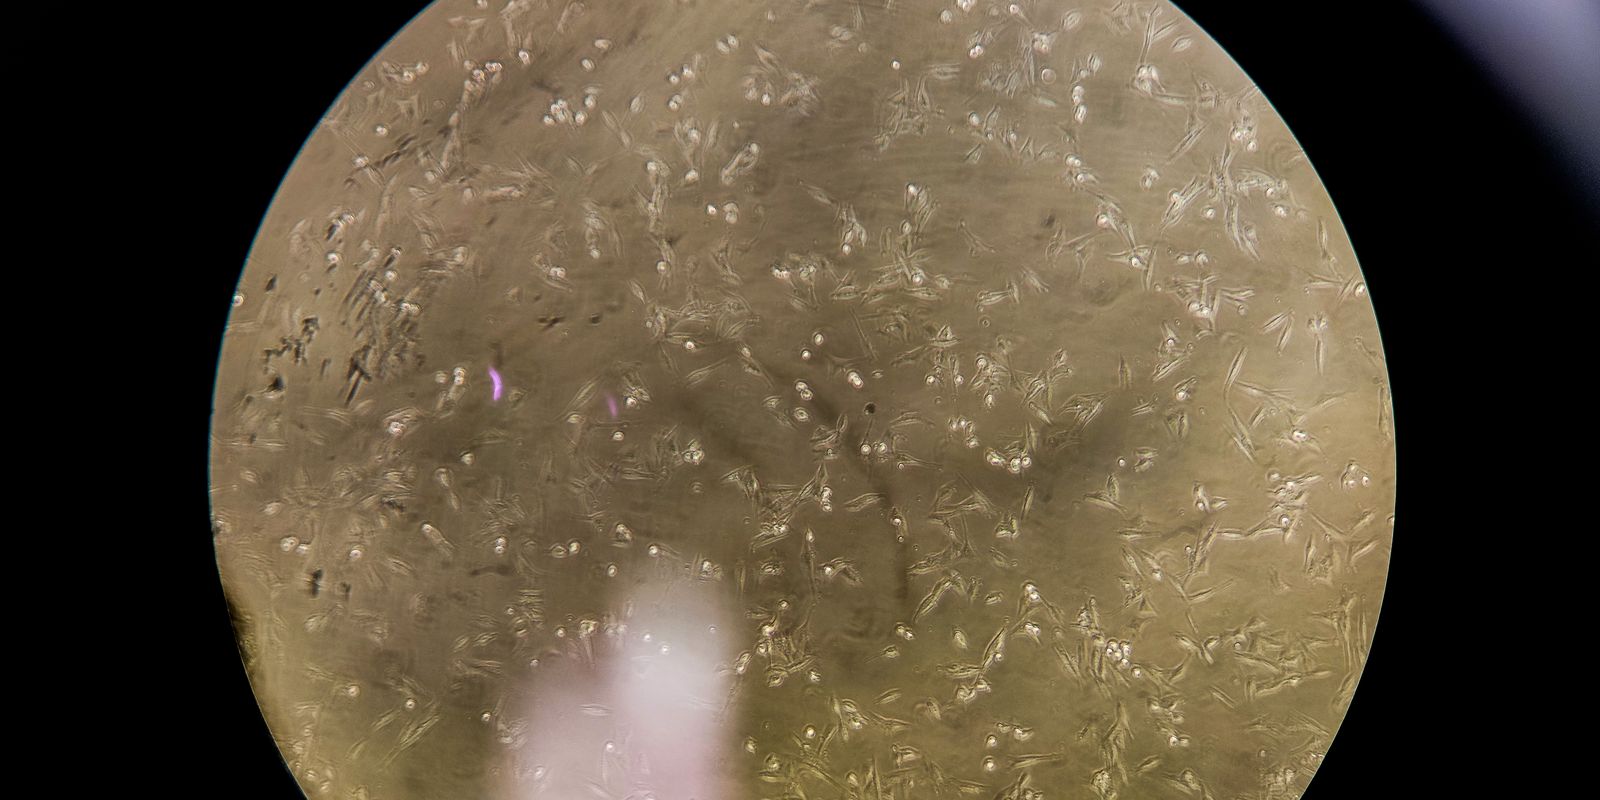

O estudo feito em camundongos adultos demonstrou pela primeira vez que o vírus invade o hipotálamo, desencadeando uma resposta inflamatória que prejudica a sinalização da insulina e altera o equilíbrio da glicose.

Embora os marcadores inflamatórios retornem aos níveis normais até 30 dias após a infecção, a resistência à insulina persiste, sugerindo uma disfunção metabólica de longo prazo. Entre as consequências estão infecções virais com potenciais fatores de risco para distúrbios metabólicos, como obesidade e diabetes tipo 2.